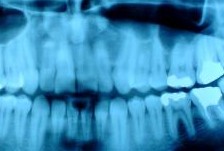

Specific professional

activities of the dental hygienist include initial

screening examination and charting of each patient's

teeth, soft tissue and other oral structures;

removal of calculus and plaque from above and below

the gumline; application of caries-preventive agents

such as fluoride and dental sealants; plaque control

instruction and development of individualized oral

hygiene programs for home care.

Other professional activities might include

gathering data for the dental diagnosis, such as:

patient medical history; dietary analysis, dental

X-ray exposure, processing and interpretation;

placement of temporary fillings and periodontal

dressings; removal of sutures; and office

management. |